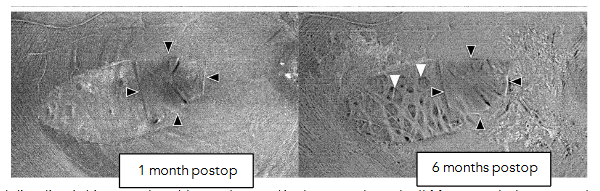

On en face OCT, they appear as multiple dark dots along the course of RNFL, called concentric macular dark spots (CMDSs), and on cross sectional OCT they appear as dimples in the inner retinal layers called dissociated optic nerve fiber layer (DONFL). CMDS were mostly found on the temporal side of the macula within two months after the ILM peeling procedure. The lesion progresses within 6 months after the surgery but remains unchanged after 12 months.

Changes in thickness of the RNFL after ILM peeling: It was found that there is an increase in RNFL thickness, only in the area nasal to fovea, where ILM was peeled, 1 month postoperatively, with subsequent reduction in thickness at 6 months postoperatively. This was attributed to the early inflammatory responses with subsequent reduction of thickness secondary to the damage inflicted to the macular retinal nerve fiber layer as a result of ILM peeling.